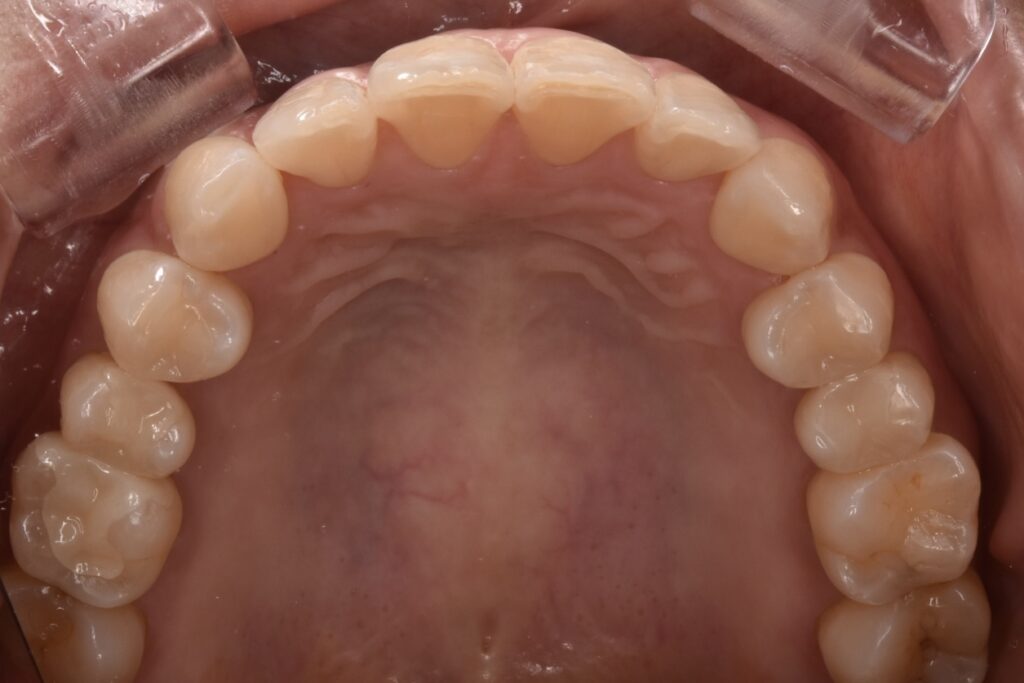

40代女性 他院でマウスピース矯正をされた後、当院で銀歯のやりかえをご相談くださいました。やりかえ希望は上の歯で5本、下の歯で1本です。

治療前後

通院回数3回 ①初回治療で左上やりかえ開始 ②左上のセラミックセットと同時に右の上やりかえ開始 ③右上のセラミックインレーセットで終了です。